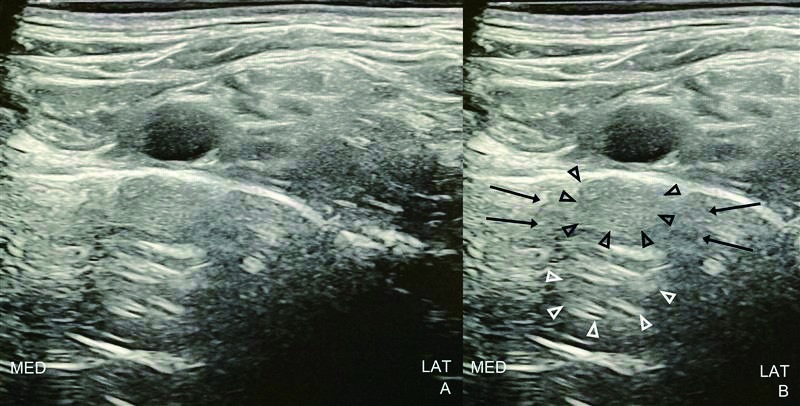

Preliminary scanning for a supraclavicular brachial plexus block showed the brachial plexus trunks lateral to the subclavian artery, above a hyperechoic line elevated from the pleura, suggesting the first rib (Figure 1 and Video 1). However, mirror-image artifacts of the subclavian artery were observed below the supposed first rib, becoming prominent during respirations.

Fig. 1. Sonography of Supraclavicular Approach for Brachial Plexus Block

Panel A shows an unannotated view. Panel B marks the mirror image artifact (black arrowheads), secondary reverberation artifact (white arrowheads), and acoustic shadowing flanking these artifacts (black arrows) deep to the subclavian artery. Abbreviations: LAT, lateral; MED, medial.